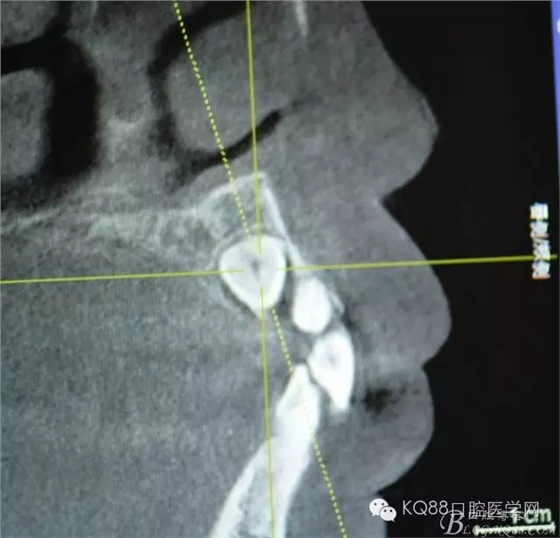

圖4.縱剖面顯示23位于腭側(cè)

圖5.水平切面觀23位于腭側(cè)